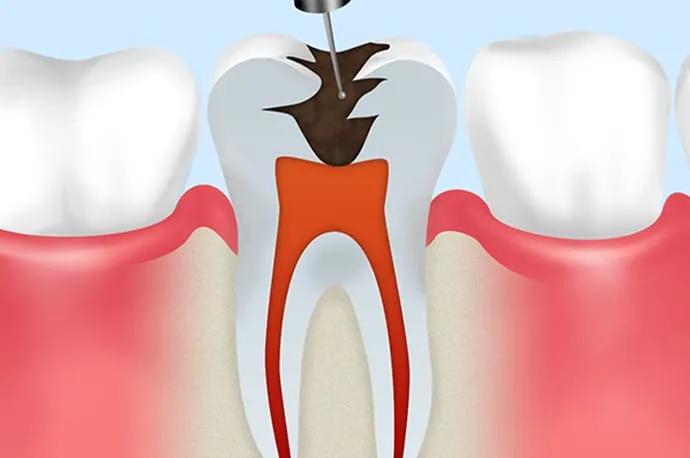

①抜髄

まだ死んでいない歯の神経を取り除く処置を抜髄といいます。虫歯や歯の破折が原因で細菌が歯の神経まで到達し、炎症を起こしている状態(歯髄炎)がこれにあたります。

原因を取り除くことで神経が回復する場合もありますが、炎症の程度によっては、早急に神経を取る必要があるケースもあります。

まだ細菌感染が成立していない段階で行う治療のため、治療の成功率は約90%とされています。

①根管拡大

ニッケルチタンロータリーファイルを使用し、根管を適切な形に広げながら、内部に存在する細菌を物理的に取り除いていきます。

②根管洗浄

根管は非常に複雑な形をしているため、器具だけでは十分な清掃ができません。そのため、次亜塩素酸ナトリウムとEDTAという2種類の洗浄液を使用し、細かく入り組んだ部分まで洗浄することで、細菌を化学的にも除去します。